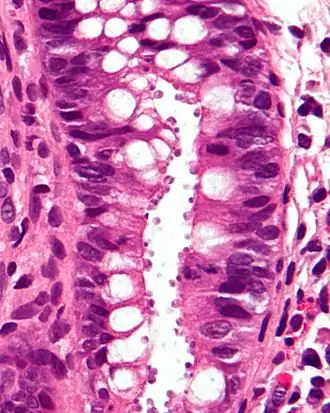

| Biópsia do cólon. Os cryptosporidium são os corpos pequenos, envolvidos, circulares, apicais, na superfície do epitélio (H&E). | |